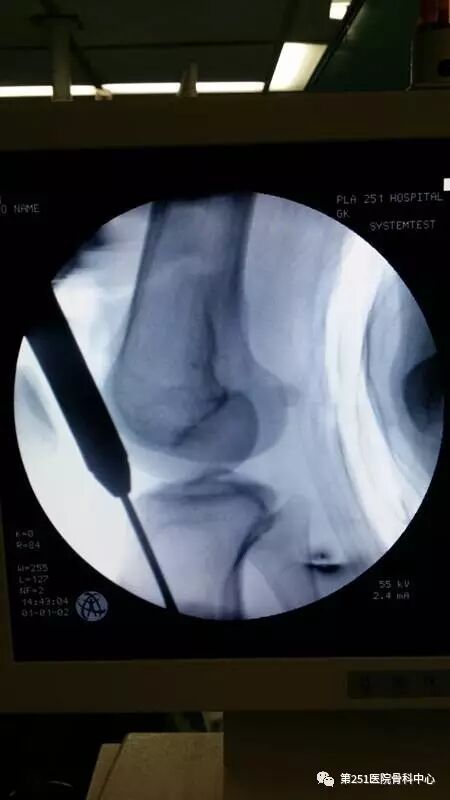

病例4:女性,车祸伤,同侧股骨、股骨颈合并胫腓骨骨折。

![]()